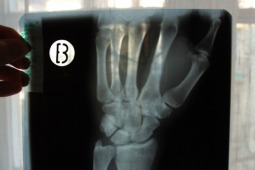

W badaniu ultrasonograficznym (usg) stawów nadgarstkowych zostaje uwidoczniony nerw pośrodkowy (NP). O zespole cieśni nadgarstka (ZCN)może świadczyć zwiększone pole przekroju NP (obrzęk nerwu) oraz wzmożony sygnał w opcji power doppler (przekrwienie). Jedną z przyczyn ograniczonego znaczenia usg w diagnozowaniu ZCN jest brak dokładnego ustalenia granicznej wartości pola przekroju NP oraz miejsca wykonywania tego pomiaru.